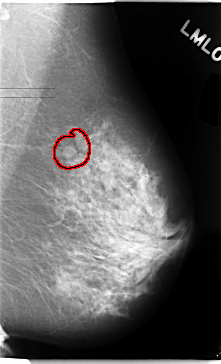

FILE: C_0102_1.LEFT_MLO.OVERLAY

TOTAL_ABNORMALITIES 1

ABNORMALITY 1

LESION_TYPE MASS SHAPE OVAL MARGINS CIRCUMSCRIBED

ASSESSMENT 3

SUBTLETY 5

PATHOLOGY BENIGN

TOTAL_OUTLINES 1

BOUNDARY